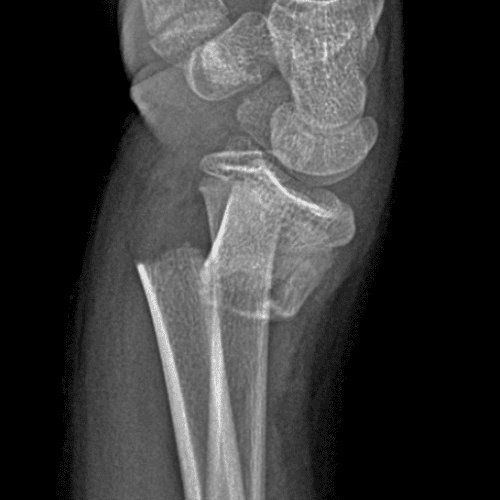

Simulates call by including subtle or difficult cases and some normals.

40 cases